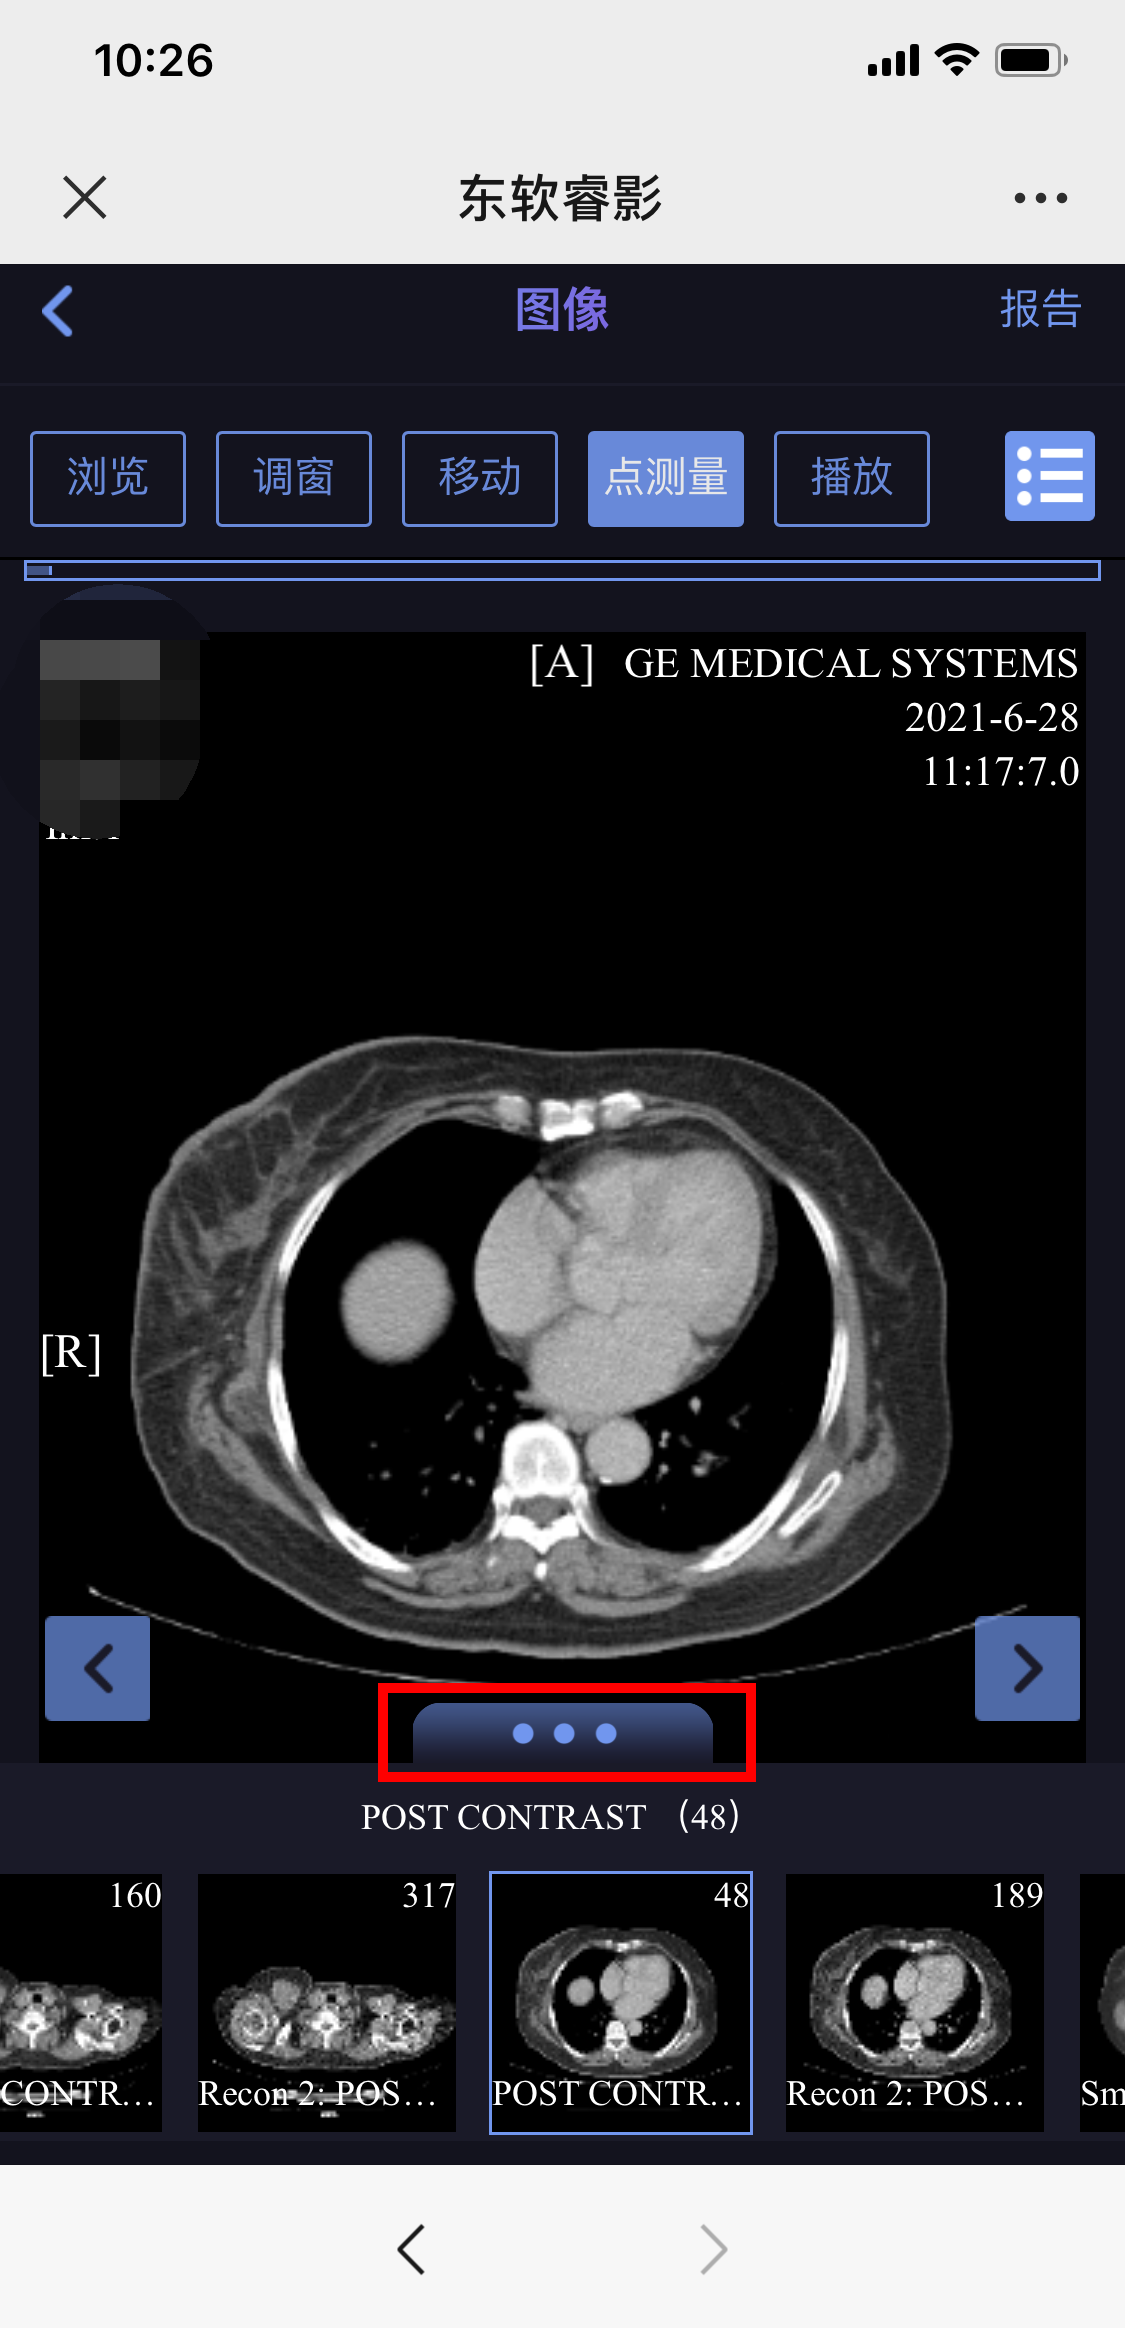

使用手机微信扫描报告左上角的二维码,按提示输入姓名、手机号码,获取云胶片(电子胶片),点击图像下方的三个圆点可以选择不同系列浏览。